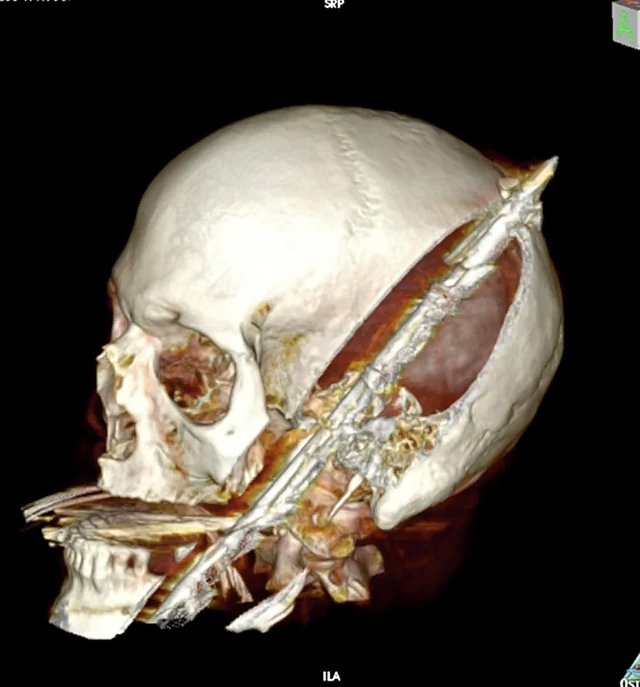

Self inflicted speargun injury to head

Ouch...poor guy...